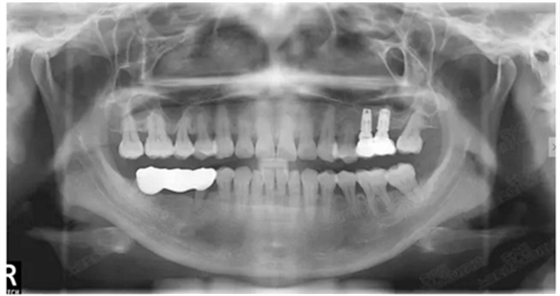

病例二

剩余骨量2mm

003.png

提升10mm